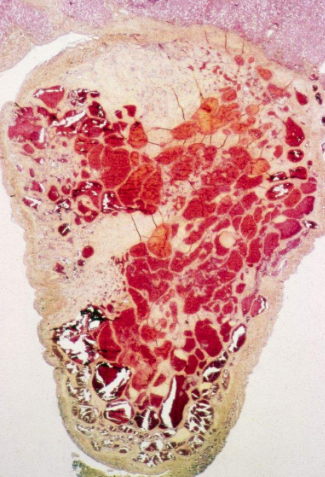

血管瘤圖片

血管瘤